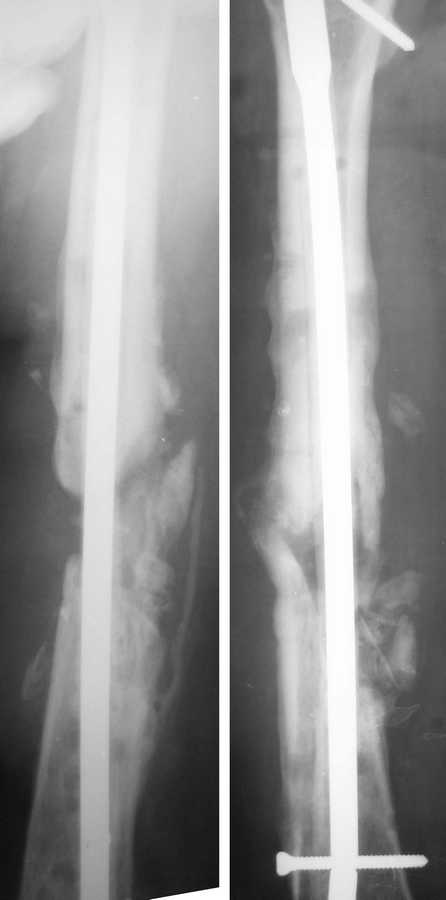

Здравствуйте дорогие коллеги.Продолжение случая. Две недели назад Павел Иванов любезно приехал в нашу больничку и прооперировал пациентку.Сначала разрезом около 10 см вскрыли зону ложного сустава. Мощные рубцы, отсутствие инфекционных очагов. Особо углубляться не стали, ушили рану, выполнили остеосинтез стержнем, предварительно покрыв его цементом с антибиотиками.Послеоперационные снимки - в приложении.Всё было хорошо. Ранняя активизация, нагрузка с костылями, постепенное увеличинеие движений в колене. На 8 сутки - повышение температуры, эвакуировали серому около 100 мл из области раны, в последующем скудное негнойное отделяемое. Впринципе постепенно затягивается.Отсутствие болей, уменьшение отёка, увеличение движений в колене, но как и до операции - температура до 37,8 в середине дня. Думаю, всё-таки какое-то инородное тело нельзя исключить. Но сейчас в любом случае контроль, ожидание сращения и ЛФК.

Из вариаций на ту же тему - недавно был в ЦРБ г. Almada (Португалия), где шеф травматологического отделения знакомый многим Nuno C. Lopes. Они там использют гвозди не покрытые, а заполненные цементом с антибиотиком. Для выхода антибиотика наружу в гвозде сделаны не очень многочисленные отверстия. Картинка в приложении.

С одной стороны, концентрация антибиотика вокруг явно меньше, с другой - выходит наружу дольше, и гвоздь можно взять толще. Отмечают частые

обострения инфекции после имплантации, но вскоре они затихают.